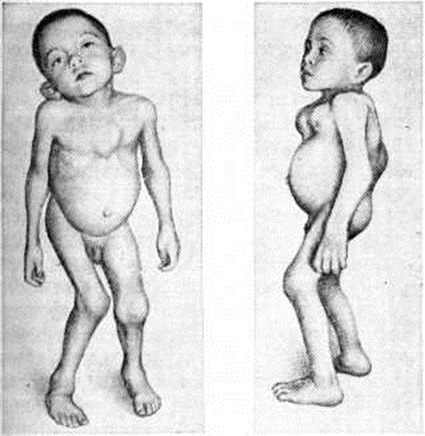

Моркио болезньМоркио болезнь (L. Morquio, уругвайский педиатр, 1867—1935; синонимы: Мукополисахаридоз тип IV, синдром Моркио — Брейлсфорда, множественный энхондральный дизостоз, деформирующая остеохондродистрофия) — наследственное заболевание соединительной ткани из группы мукополисахаридозов, характеризующееся множественными поражениями скелета, низким ростом, кератансульфатурией. Заболевание впервые описали в 1929 год независимо друг от друга Моркио и Брейлсфорд (J. F. Brailsford). До 1959 год к Моркио болезнь относили различные множественные поражения скелета, в том числе спондилоэпифизарную дисплазию, множественную эпифизарную дисплазию и другие В самостоятельную нозологический форму Моркио болезнь выделена после обнаружения специфического биохимический признака — наличия в моче мукополисахаридов. Частота Моркио болезнь примерно 1 : 40 000 среди новорожденных. Этиология и патогенез. Тип наследования — аутосомно-рецессивный. Патогенез связан с нарушением катаболизма кислых гликозамингликанов (мукополисахаридов) вследствие дефицита фермента — хондроитинсульфата-N-ацетил-гексозоаминсульфатсульфатазы. Клиническая картина. Первые симптомы появляются к концу первого — началу второго года жизни. Наблюдается гротескность черт лица, гипертелоризм (смотри полный свод знаний Дизостоз), седловидный нос, мегалоглоссия, мышечная слабость, отставание в двигательном развитии. Отмечается диффузная гипотрофия и дряблость мышц, изменение походки от лёгкой хромоты до утиной. К 3—4 годам формируются грубые костно-суставные деформации грудной клетки (куриная, бочкообразная, килеобразная), позвоночника (сколиоз и кифосколиоз), вальгусная деформация конечностей (рисунок 1). Замедляется темп роста, шея и туловище — короткие. К 7 —10 годам у некоторых детей появляются боли в конечностях, возникают контрактуры в локтевых, плечевых, коленных суставах. Миопатический симптомокомплекс нарастает; дети жалуются на слабость, утомляемость в состоянии покоя, снижение мышечной силы. Определяются признаки внутричерепной гипертензии (смотри полный свод знаний Гипертензивный синдром), вегетативная лабильность, повышение сухожильных рефлексов вследствие постепенного развития центральных парезов и параличей (смотри полный свод знаний Параличи, парезы). Психическое развитие, как правило, нормальное. При осмотре глазного дна выявляется атрофия диска зрительного нерва (смотри полный свод знаний). Диагноз устанавливается на основании клинические, картины, биохимический исследования мочи и рентгенологическое данных. В моче обнаруживается избыточная экскреция общего количества кислых гликозамингликанов, в частности кератансульфата. При рентгенологическое исследовании длинных и коротких трубчатых костей наблюдается нарушение роста эпифизов костей, проявляющееся в их уплощении, расширении и уменьшении высоты (рисунок 2) при отсутствии существенного торможения роста в эпифизарных хрящах. При рентгенографии позвоночника, как правило, обнаруживается заметное уплощение и расширение тел позвонков от CII до Lv — платибрахиспондилия (рисунок 3), чем и объясняется характерное укорочение туловища и необычно короткая шея при Моркио болезнь; межпозвоночные диски при этом мало изменены или не изменены вовсе. Переднезадний размер грудной клетки увеличен, межрёберные промежутки сужены, грудина дугообразно деформирована. Все эти изменения выявляются при обзорной (желательно телевизионной) рентгеноскопии с последующей обязательной рентгенографией тех отделов скелета, в которых обнаруживаются наиболее выраженные изменения. Дифференциальный диагноз следует проводить с другими типами мукополисахаридозов (смотри полный свод знаний), несовершенным остеогенезом (смотри полный свод знаний Остеогенез несовершенный), спондилоэпифизарными и метафизарными дисплазиями, витамин D-резистентным рахитом (смотри полный свод знаний Фосфат-диабет), почечным рахитом (смотри полный свод знаний Остеопатия нефрогенная), врождённым сифилисом (смотри полный свод знаний), гипотиреозом (смотри полный свод знаний). Лечение. Лечению подлежат больные с легкоустранимыми или стойкими деформациями конечностей, контрактурами, анкилозом суставов в порочном положении, вывихами и подвывихами в суставах, приводящими к нарушениям формы и функции конечностей. Лечение может быть консервативное и оперативное. Выбор метода лечения зависит от тяжести заболевания, возраста и общего состояния больного. |

Рис. 2. | ||